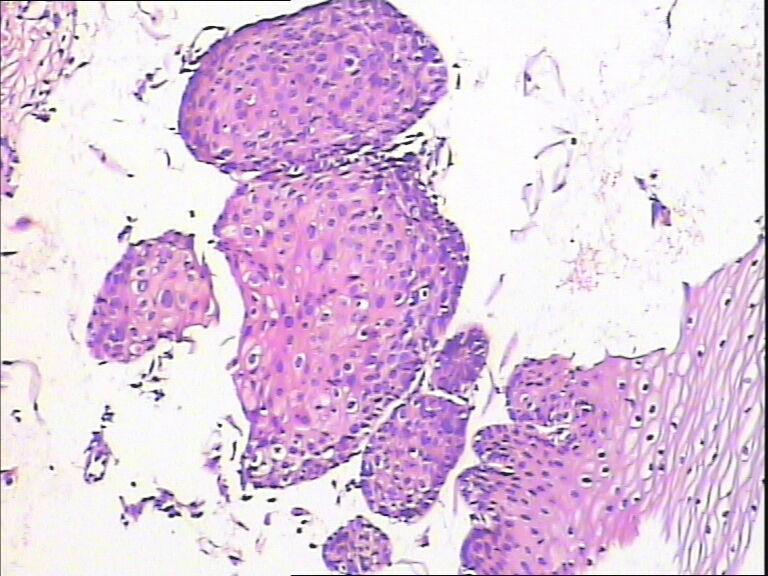

45y,触血,宫颈多点活检。

不同级别的CIN,局灶已达到CIN3。

湿疣改变

HPV感染。局部已达到CIN2-3

CINⅡ,提示HPV感染。

慢性宫颈炎伴HPV感染改变、腺体鳞状化生。

HPV感染。灶性CIN2-3